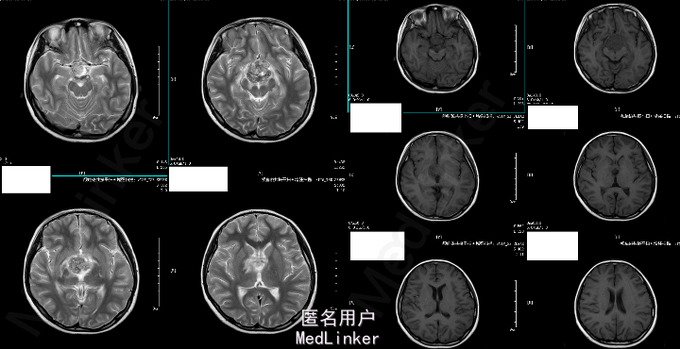

女 11岁 学生 主诉:2014年5月无明显诱因出现头晕,偶有头痛,双眼视力下降,步态正常。外院头颅MRI提示“鞍上占位性病变,累及蝶鞍,多为生殖细胞瘤,不完全除外颅外咽鼓管瘤”。 既往史、个人史、家族史未见异常。

T 36.1℃ P 80bpm,R 20bpm,BP 100/65mmHg。心肺腹未见明显异常。神经查体未见命像一场。 辅助检查:2014-06-20外院头颅MRI:鞍上占位性病变,累及蝶鞍,多为生殖细胞瘤,不完全除外颅外咽鼓管瘤 2014-07-08我院头颅MR增强:鞍区占位性病变,考虑生殖细胞来源的肿瘤可能性大。 b-HCG 13.53ng/ml,AFP 224.84ng/ml。